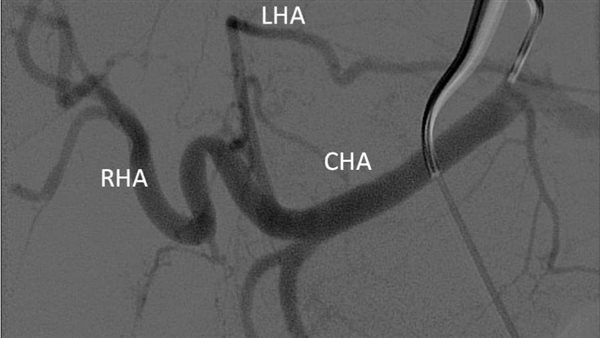

وتعتبر هذه العملية الأول من نوعها يتم علاجها من خلال جهاز الأشعة المقطعية ١٢٨ متعدد المقاطع حيث تم علاج الورم من خلال قسطرة بالشريان الكبدي للفص الأيسر من الكبد ونجاح عملية الحقن التي تظهر اختفاء الأوعية الدموية المغذية للورم.